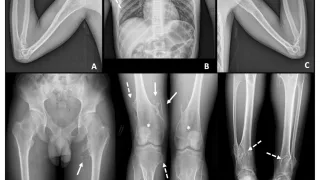

手術日+782日目 2026/4/20(月)(指骨骨髄炎)

午前の病院での仕事今朝は晴れ.気温は, 13 ℃と低めでした.8時前に病棟に上がって, 電子カルテを確認.昨晩は, 当院が整形外科の救急輪番でしたが, 救急車はゼロでした.夜勤だった後輩整形外科から電話連絡があり.隣の市から橈骨遠位端骨折の...